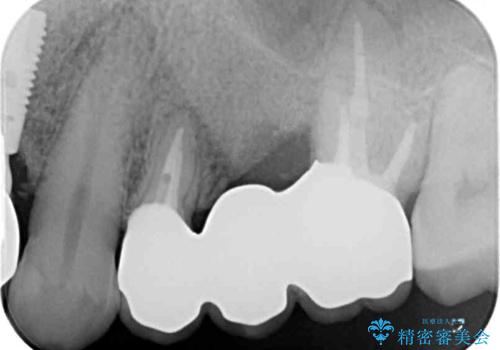

レントゲン写真より、歯が破折している可能性が示唆され、歯槽骨が大きく欠損している様子が分かりました。

3歯のクラウンを除去し、破折が疑われる歯をチェックしたところ、予想通り破折していたため、抜去することとしました。

インプラントによる補綴治療も検討しましたが、骨吸収量が多いこと、後方の支台歯が今後抜歯となる可能性が否定できないことを鑑み、将来抜歯となった際にインプラント2本を埋入することで患者様と事前にお話をしました。